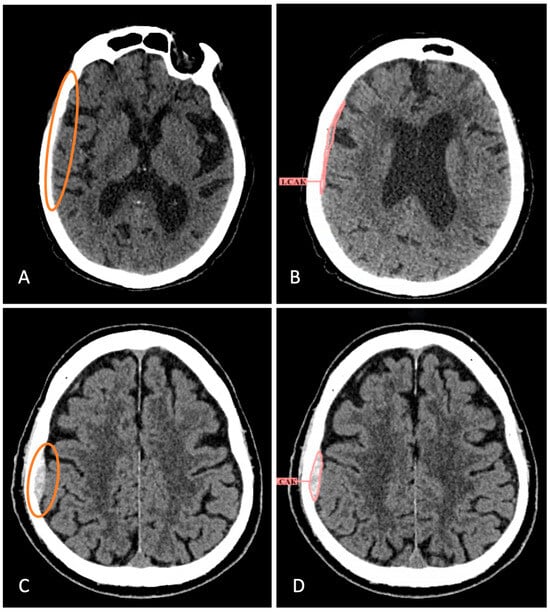

2.4. AI Services

3.1. Comparison of AI Services Among Themselves

3.2. Comparison of AI and Radiologists